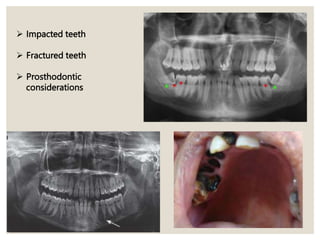

 Impacted teeth

 Fractured teeth

 Prosthodontic

considerations